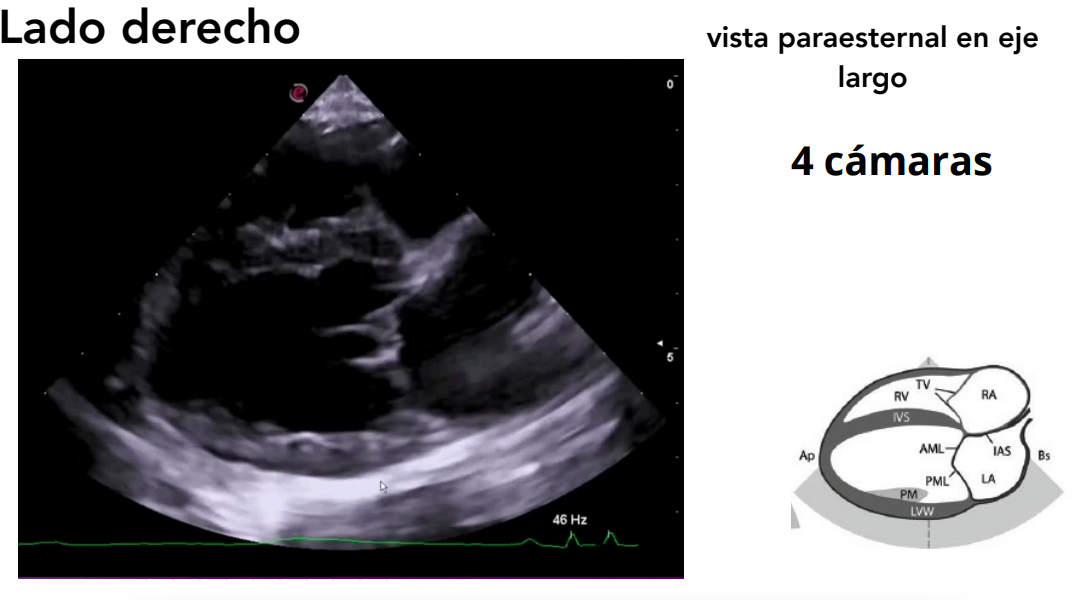

1. Lado derecho

Posición: decúbito lateral derecho.

- El transductor se coloca en el 4º-5º espacio intercostal, a 1–5 cm del borde esternal. Por eso se llama paraesternal.

- Se obtienen vistas paraesternales (ejes largos y cortos).

- Largo (longitudinal): del eje base–ápex.

Vista paraesternal en eje largo

- 4 cámaras y 5 cámaras (incluye tracto de salida del VI).

- Evaluación de:

- Válvulas mitral, tricúspide y aórtica.

- Regurgitaciones valvulares.

- Defectos en septos interatrial e interventricular.